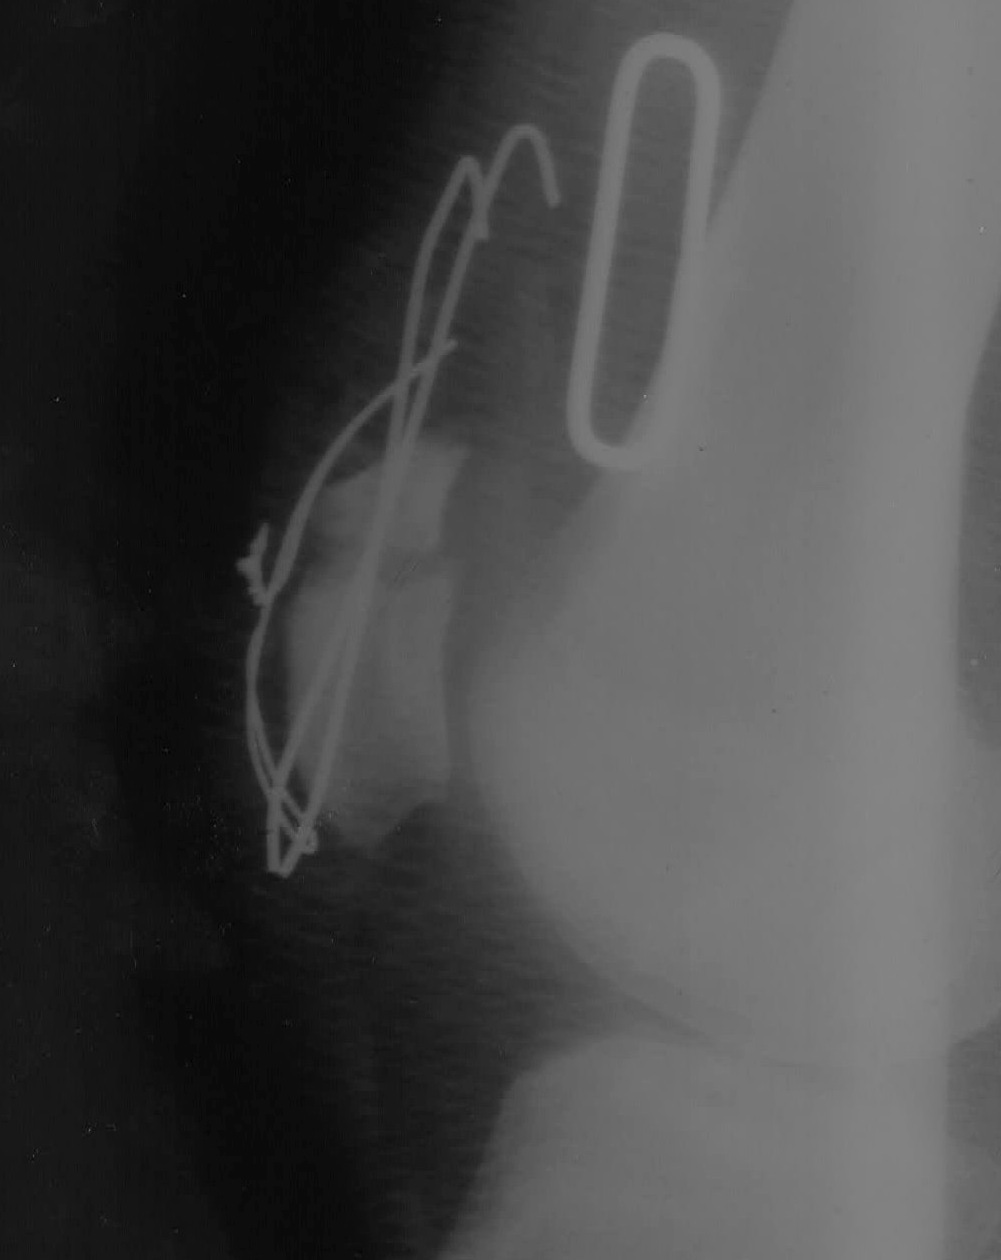

[Ortho] Рефрактура надколенника

После рентгенконтроля и оценки повторного перелома было принять решение

(оперирующим хирургом) лечить в ортезе консервативно

Было показано оперативное лечение - последнее выполнялось мною

Отломки были максимально "освежены" от рубцово-измененных тканей,

тунелизированы (каждый пройден сверлом в 5-7 местах) и адаптированы

между собой

Имеется рентгенологический диастаз (хотя клинически "стянул" проволоку

максимально (3 раза перед этим лопала при пробе большего стягивания или

сгибания в коленном суставе больше 40 градусов))

После операции сустав в ортезе, осевая нагрузка дозированная на костылях